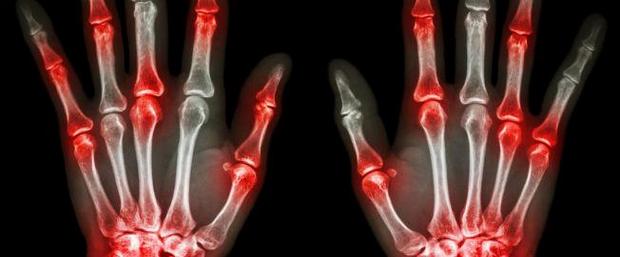

Η Ρευματοειδής αρθρίτιδα (ΡΑ) είναι μια συχνή μορφή αρθρίτιδας. Προκαλεί φλεγμονή στις αρθρώσεις οι οποίες εμφανίζονται θερμές, διογκωμένες, πονούν, μπορεί να είναι ερυθρές και έχουν μειωμένο εύρος κίνησης.

Είναι χρόνια νόσος, προσβάλλει σχεδόν όλες τις αρθρώσεις του σώματος και το αποτέλεσμα της είναι η καταστροφή του χόνδρου των οστών, των τενόντων και συνδέσμων τους.

Όσοι έχουν ΡΑ παρατηρούν ότι οι αρθρώσεις τους είναι ζεστές, διογκωμένες, ευαίσθητες στο άγγιγμα ή την πίεση, μπορεί να έχουν ερυθρό χρώμα, πονούν και δύσκαμπτες. Αυτά τα σημεία της αρθρίτιδας οφείλονται στη φλεγμονή του υμένα και του θυλάκου που καλύπτει τις αρθρώσεις.

Αν η φλεγμονή αυτή παραμείνει αθεράπευτη ή δεν ανταποκρίνεται στη θεραπεία και επιμένει τότε ακολουθεί καταστροφή του χόνδρου των οστών των τενόντων και των συνδέσμων. Αυτό προκαλεί παραμόρφωση των αρθρώσεων και ανικανότητα που συνήθως είναι μόνιμα.

Συνήθως οι αρθρώσεις προσβάλλονται συμμετρικά δηλαδή και στις δύο πλευρές του σώματος χωρίς αυτό να είναι αποκλειστικό.

Οι ακτινογραφίες στην αρχή της νόσου μπορεί να είναι φυσιολογικές και τα ευρήματα να εμφανισθούν αργότερα. Τα κυριότερα ευρήματα είναι η οστεοπόρωση γύρω από τις αρθρώσεις που πάσχουν, η στένωση του διαστήματος των αρθρώσεων και οι διαβρώσεις που συνήθως είναι συμμετρικές όπως προαναφέρθηκε.